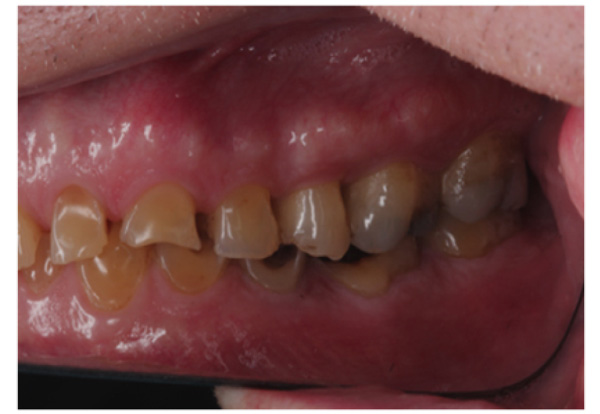

The patient presented with competent lips, an average lip line, normal TMJ function, and a mild Class II Division I incisor relationship with an increased overbite. The preoperative pan-oral radiograph is shown in Fig. (1). Boney exostoses and a large mandibular torus in the lower right mandible were present. The intra-oral presentation of the teeth is shown in Figs. (2-6). The patient had good oral hygiene and a healthy periodontium. The teeth had a glossy, smooth, and glazed appearance, showing cupping of the occlusal surfaces with significant loss of hard tissue and yellow color from the underlying dentine. This presentation was indicative of severe generalized tooth wear with exposed dentine in all sextants. The palatal, occlusal, and incisal surfaces were mainly affected, with lower buccal surfaces exhibiting more wear than the lower lingual, resulting in a reverse curve of Monson. The maximum BEWE score of 18 was recorded, meaning that the tooth with the most severe wear in each sextant had greater than 50% surface loss [9]. Several posterior teeth had amalgam restorations with defective margins (FDI 16, 26, 27, 37, and 47), as shown in Figs. (5 and 6). All teeth responded normally to pulp sensibility tests (cold test). The radiographs did not show any apical pathology to be present, but the pan-oral shows the scooped-out appearance of the lower molars.

IPS Empress Direct ® (Ivoclar Vivadent, Schaan, Liechtenstein) composite was syringed onto the worn surface and into the stent,which was seated onto the tooth. The composite was cured through the stent for 20 seconds; then the stent was removed, and the composite curing light was used again to ensure afull set for a further 40 seconds. The PTFE tape was removed, the excess composite at the gingival margin was trimmed back with narrow and ultra-fine diamond finishing burs, and a final polish was performed using Shofu Super-Snap Rainbow® discs (Kyoto 605-0983, Japan). The resultsare shown in Figs. (8-10). The slight increase in the vertical dimension is seen when comparing the pre-operative frontal image (Fig. 2) with the post-op image (Fig. 8), where some of the labial surfaces of the lower incisors is now visible, which was planned from the outset.